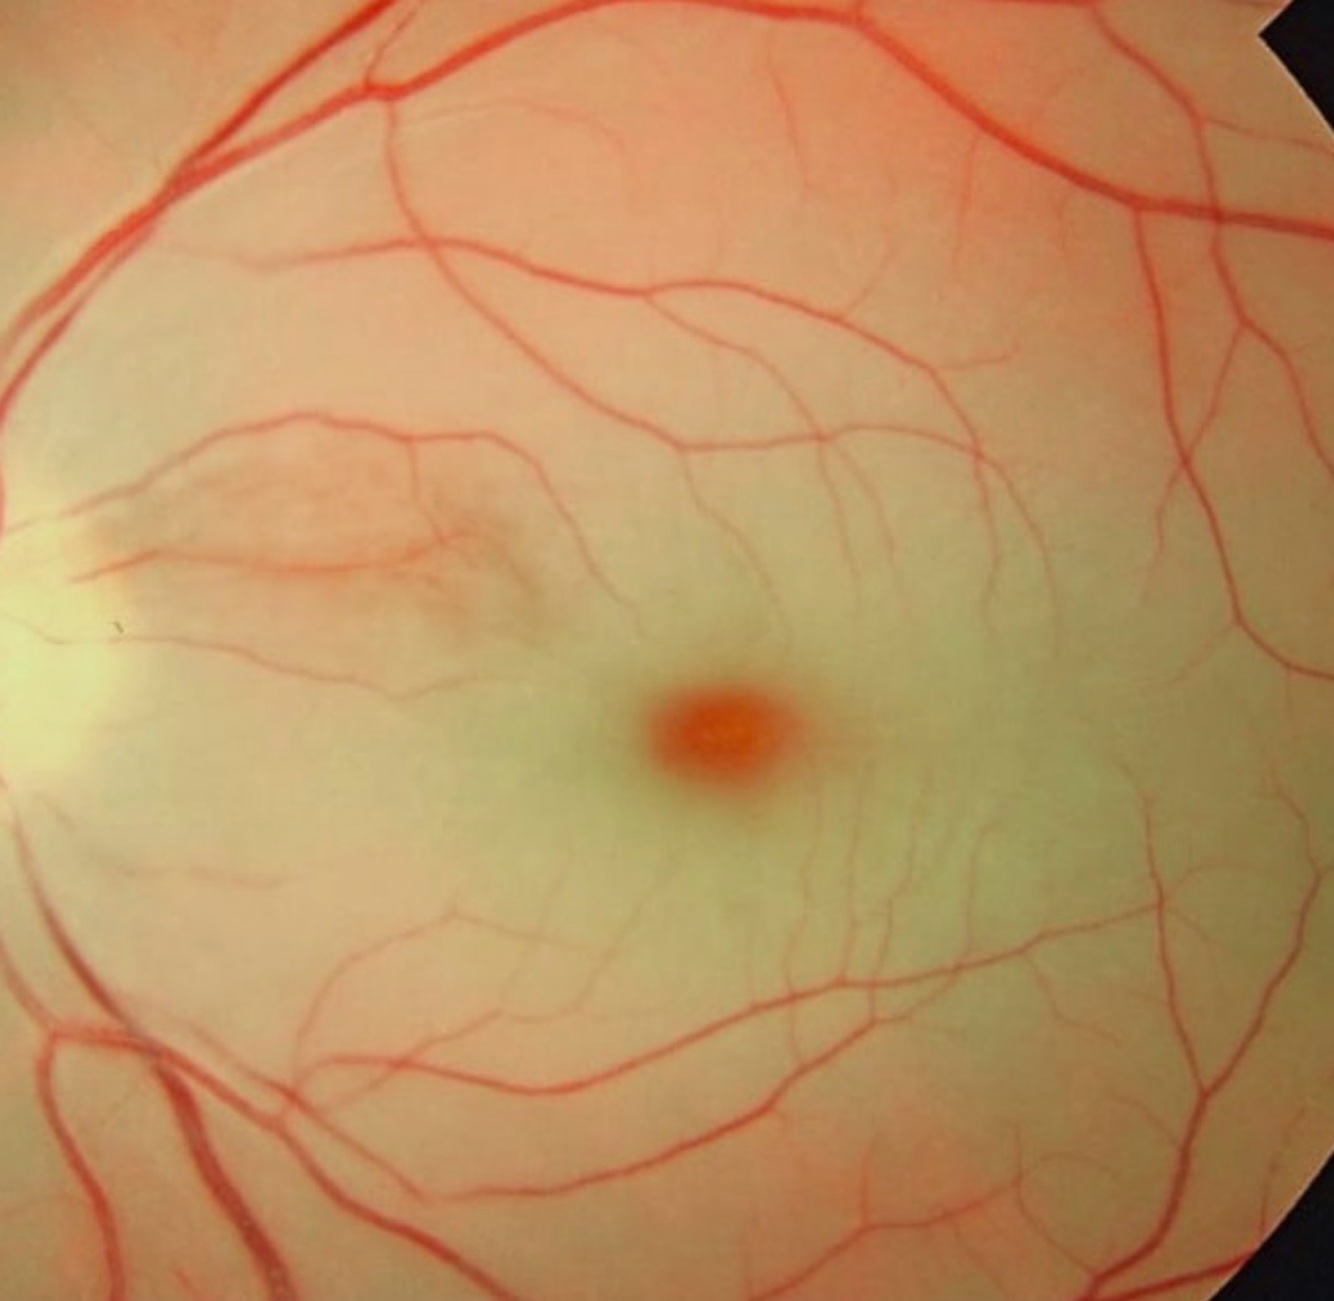

What are the initial symptoms of Central Retinal ARTERY occlusions?

• Painless vision loss

• CHERRY-RED macula

• APD

APD stands for Afferent Pupillary Defect.

Instead, the fovea receives its blood supply from the underlying choroid, which is a separate, rich vascular network supplied by the ciliary arteries.

• Because the choroidal circulation is typically not affected by the central retinal artery occlusion, the fovea remains perfus